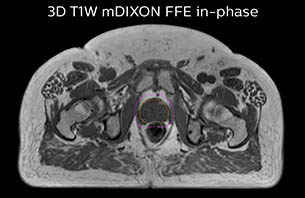

A 77-year-old male with prostate cancer cT3aN0M0, Gleason 8 and PSA 52 μg/L referred to androgen deprivation and radiation therapy with a prescribed dose of 50 Gy to the pelvic lymph node regions and 76 Gy to the prostate.

MR-only simulation workflow The 3D T1W FFE mDIXON sequence provides in-phase, water and fat images in one acquisition. Target and organs-at-risk are delineated on the 3D T2W TSE images. Prostate GTV is shown in orange, PTV in purple. The 3D bFFE sequence is used by the planner to mark the position of the fiducial markers (gold anchors) and contours are transferred to the digitally reconstructed radiographs (DRRs).